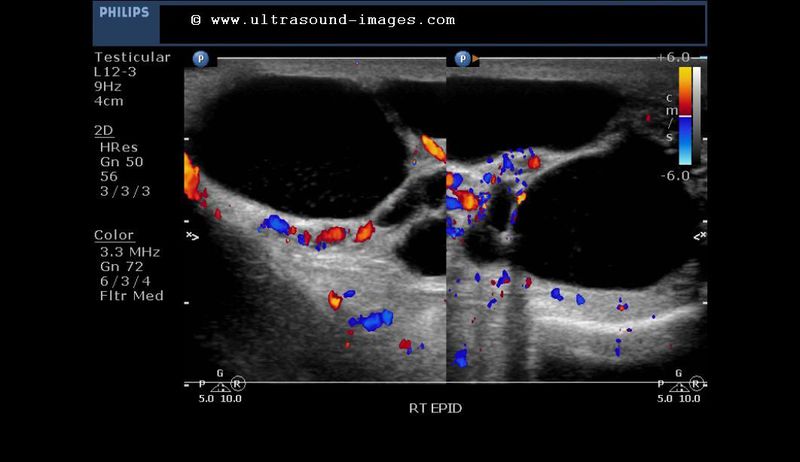

The left scrotum shows a large extratesticular varicocele (long arrow in image on left). Also present are a few dilated vessels (more than 2 mm. each) in the subcapsular part of the left testes (small arrow in color Doppler image). Spectral Doppler trace of the vessels show typical low resistance venous flow pattern. These Color Doppler and spectral Doppler ultrasound images are diagnostic of intratesticular varicocele of left testes. This appears to communicate with the Extratesticular varicocele. Color Doppler helps to rule out other lesions like tubular ectasia of rete testes and Testicular neoplasia which can cause similar appearances on sonography. Both above images are courtesy of Ravi Kadasne, MD, UAE.